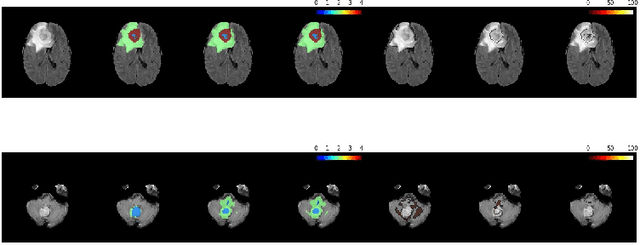

Abstract:Automation of brain tumor segmentation in 3D magnetic resonance images (MRIs) is key to assess the diagnostic and treatment of the disease. In recent years, convolutional neural networks (CNNs) have shown improved results in the task. However, high memory consumption is still a problem in 3D-CNNs. Moreover, most methods do not include uncertainty information, which is especially critical in medical diagnosis. This work studies 3D encoder-decoder architectures trained with patch-based techniques to reduce memory consumption and decrease the effect of unbalanced data. The different trained models are then used to create an ensemble that leverages the properties of each model, thus increasing the performance. We also introduce voxel-wise uncertainty information, both epistemic and aleatoric using test-time dropout (TTD) and data-augmentation (TTA) respectively. In addition, a hybrid approach is proposed that helps increase the accuracy of the segmentation. The model and uncertainty estimation measurements proposed in this work have been used in the BraTS'20 Challenge for task 1 and 3 regarding tumor segmentation and uncertainty estimation.

Abstract:Automation of brain tumors in 3D magnetic resonance images (MRIs) is key to assess the diagnostic and treatment of the disease. In recent years, convolutional neural networks (CNNs) have shown improved results in the task. However, high memory consumption is still a problem in 3D-CNNs. Moreover, most methods do not include uncertainty information, which is specially critical in medical diagnosis. This work proposes a 3D encoder-decoder architecture, based on V-Net \cite{vnet} which is trained with patching techniques to reduce memory consumption and decrease the effect of unbalanced data. We also introduce voxel-wise uncertainty, both epistemic and aleatoric using test-time dropout and data-augmentation respectively. Uncertainty maps can provide extra information to expert neurologists, useful for detecting when the model is not confident on the provided segmentation.